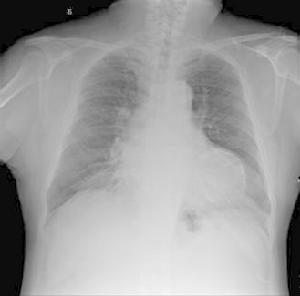

3.X 線檢查 見心影普遍增大,透視可見心臟搏動幅度減小,或有心包積液徵象。

老年甲減性心臟病X線檢查2.甲減病因的鑑別 即區別原發性、中樞性和周圍性甲減。